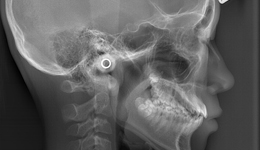

矯正治療を正確に行うために、頭部を前と横からレントゲン撮影できる“セファログラム(頭部X線規格写真)”を導入しています。

これにより、大学病院と同レベルの精度の高い治療が可能になります。